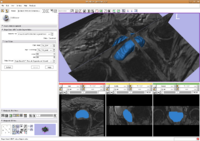

Simultaneous Multiple Object Segmentation using Robust Statistics FeaturesMultiple objects are segmented simultaneously using several interactive active contours based on the feature image which utilizes the robust statistics of the image. More... New: Y. Gao, S. Bouix, M. Shenton, R. Kikinis, A. Tannenbaum. A 3D interactive multi-object segmentation tool using local robust statistics driven active contours. MedIA, volume 16, 2012, pp. 1216-1227. |